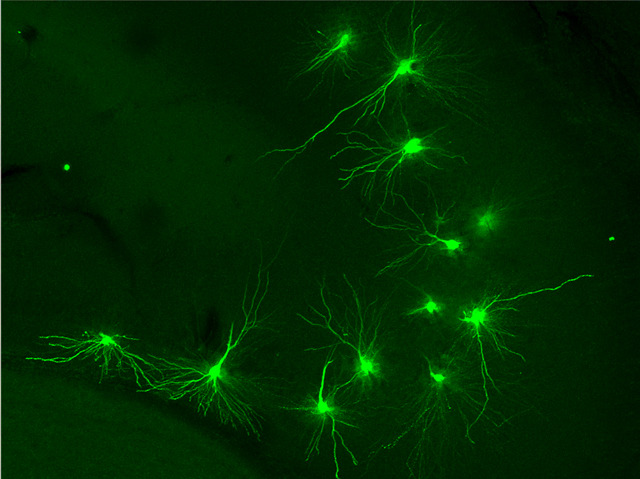

Gene for Epilepsy

Researchers learn more every day about how our genes influence our health and wellbeing. A recently described group of tiny molecules – microRNAs – can trigger or terminate the process by which genes produce proteins. MicroRNAs literally ‘mop up’ messages from genes preventing their translation into protein products. Researchers investigating microRNA-134 found it in particularly high levels in a brain region associated with epileptic seizure. They discovered this tiny molecule was blocking the expression of a gene called LIMK1. However, they used another small molecule to ‘hoover up’ microRNA-134 from the brain cells (pictured) of epileptic mice, with the result that the animals suffered fewer seizures. These results offer a glimmer of hope for epilepsy sufferers, a third of whom gain no benefit from current drug treatments. It seems likely that this drug-resistant group of patients could benefit significantly from the new approach.